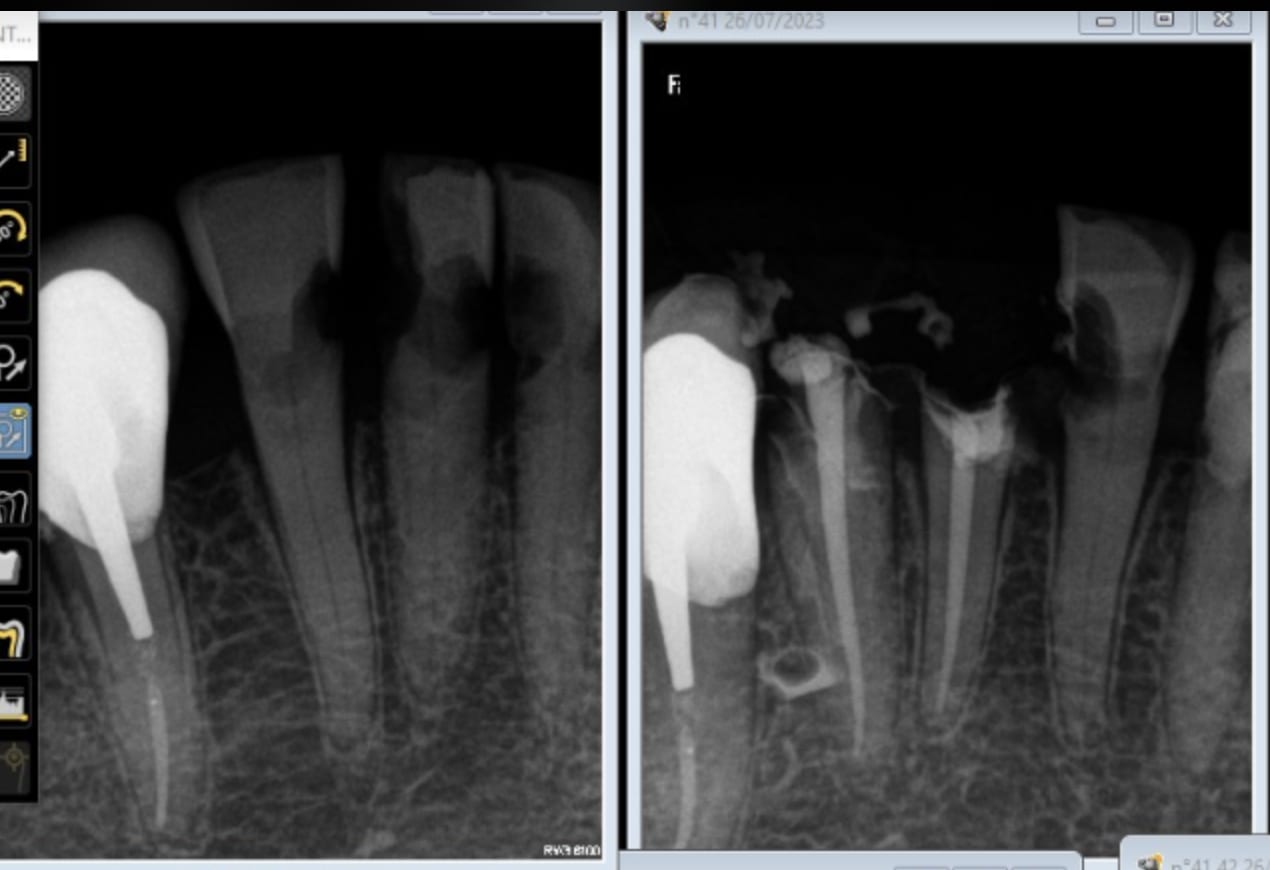

Une histoire de racine fendue ? Tu vois quoi toi, sur les radios ?

Je lui ai dit qu’il fallait reprendre 25 et extraire 26.

Pour moi c’est perforations, dépassements, fistules, douleurs, poches, furcations, espace biologique, bourrages alimentaire, forme, teinte …

Des radios comme ça on en a tous plein nos tiroirs.

On peut aussi faire comme le cas des 25/26 que j’ai montré, et là c’est pas la même.

Pour moi c’est à peu près ça qui s’est passé jusqu’à ce qu’on me montre que j’ai tort…